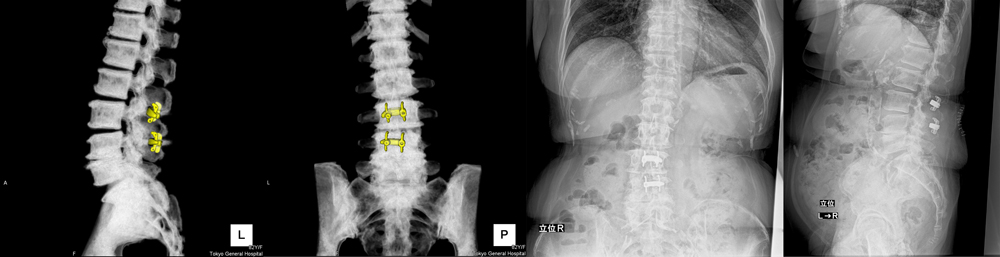

頚椎脊柱管狭窄症の症例と症状について|白石脊椎クリニック, 脊椎脊髄センター | 総合東京病院【公式】中野区 練馬区 24時間,

脊椎脊髄センター | 総合東京病院【公式】中野区 練馬区 24時間, 腰椎変性疾患 | 総合東京病院【公式】中野区 練馬区 24時間救急受入,